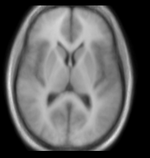

this is the probabilistic tissue atlas, to be registered to the T1

Target Brain Probabilistic Atlas

• moving: Probabilistic Tissue atlas, 0.9375 x 0.9375 x 1.5 mm axial, 256 x 256 x 124

unregistered unregistered after BSpline non-rigid registration afterAffine+ fast BSpline non-rigid registration